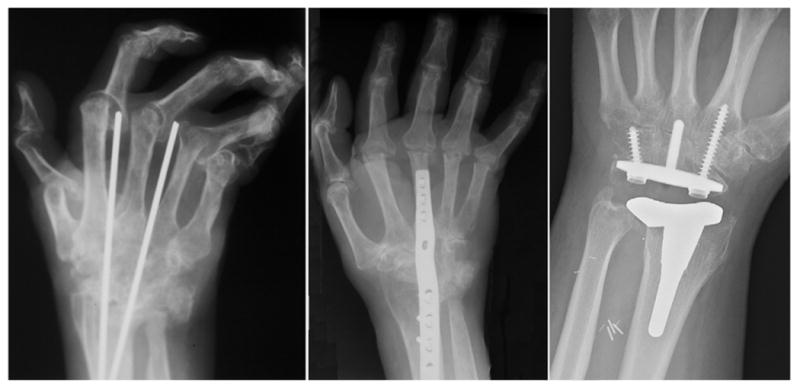

Radiocarpal articular wear requires arthroplasty or arthrodesis (Fig 5). Both procedures are indicated for deformity and instability that interfere with function or cause persistent pain. Prerequisite requirements for arthroplasty include good pre-operative wrist motion, functional wrist tendons, and good bone stock. In addition, adequate soft tissue is necessary to stabilize the wrist implant. Wrist arthrodesis is a predictable procedure and has a low complication rate. It is contraindicated in patients with severe shoulder and elbow diseases because patients may not be able to adapt to loss of motion in all three joints. Compared to arthrodesis, the post-operative rehabilitation program for arthoplasty is generally more difficult and is associated with higher risk of complications. The wrist mobility with arthroplasty is traded for the predictability with arthrodesis. Older methods of arthroplasty included the use of silicone or metal/polyethylene implants. An expanding number of total wrist replacement systems are increasing reconstructive options (6). Complications of wrist arthroplasty include fracture, infection, implant failure, implant dislocation, and implant loosening. For patients with bilateral wrist problem, arthrodesis is recommended in the dominant hand to maintain stability for gripping and power. The non-dominant hand is treated with arthroplasty to maintain some joint motion needed for self-hygiene. Destruction of the radiocarpal joint with preservation of the midcarpal joint may be treated with limited arthrodesis, which maintains about 25-50% of wrist motion through motion at the midcarpal joint.

Fig 5.

Surgical treatment options of the rheumatoid wrist includes arthodesis using Steinmann pins (left) or plating (center). Alternatively, prosthetic total wrist arthroplasty (right) can be performed.